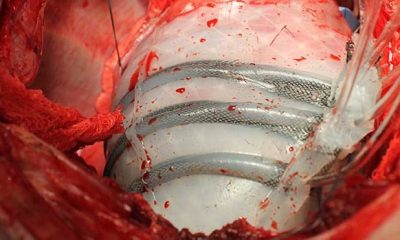

Az új „soft robot” a szívet körbe ölelve pumpál

2017. január 23. hétfőHatalmas innováció a szívelégtelenségben szenvedők számára